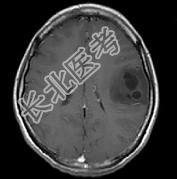

- 单项选择题女,33岁, 三个月前有右上肢及右颜面部麻木,伴耳鸣及头昏, 请根据所提供图像,诊断最有可能是 ( )

A、星形细胞瘤

B、脑血吸虫病

C、脑转移瘤

D、脑结核

E、脑脓肿